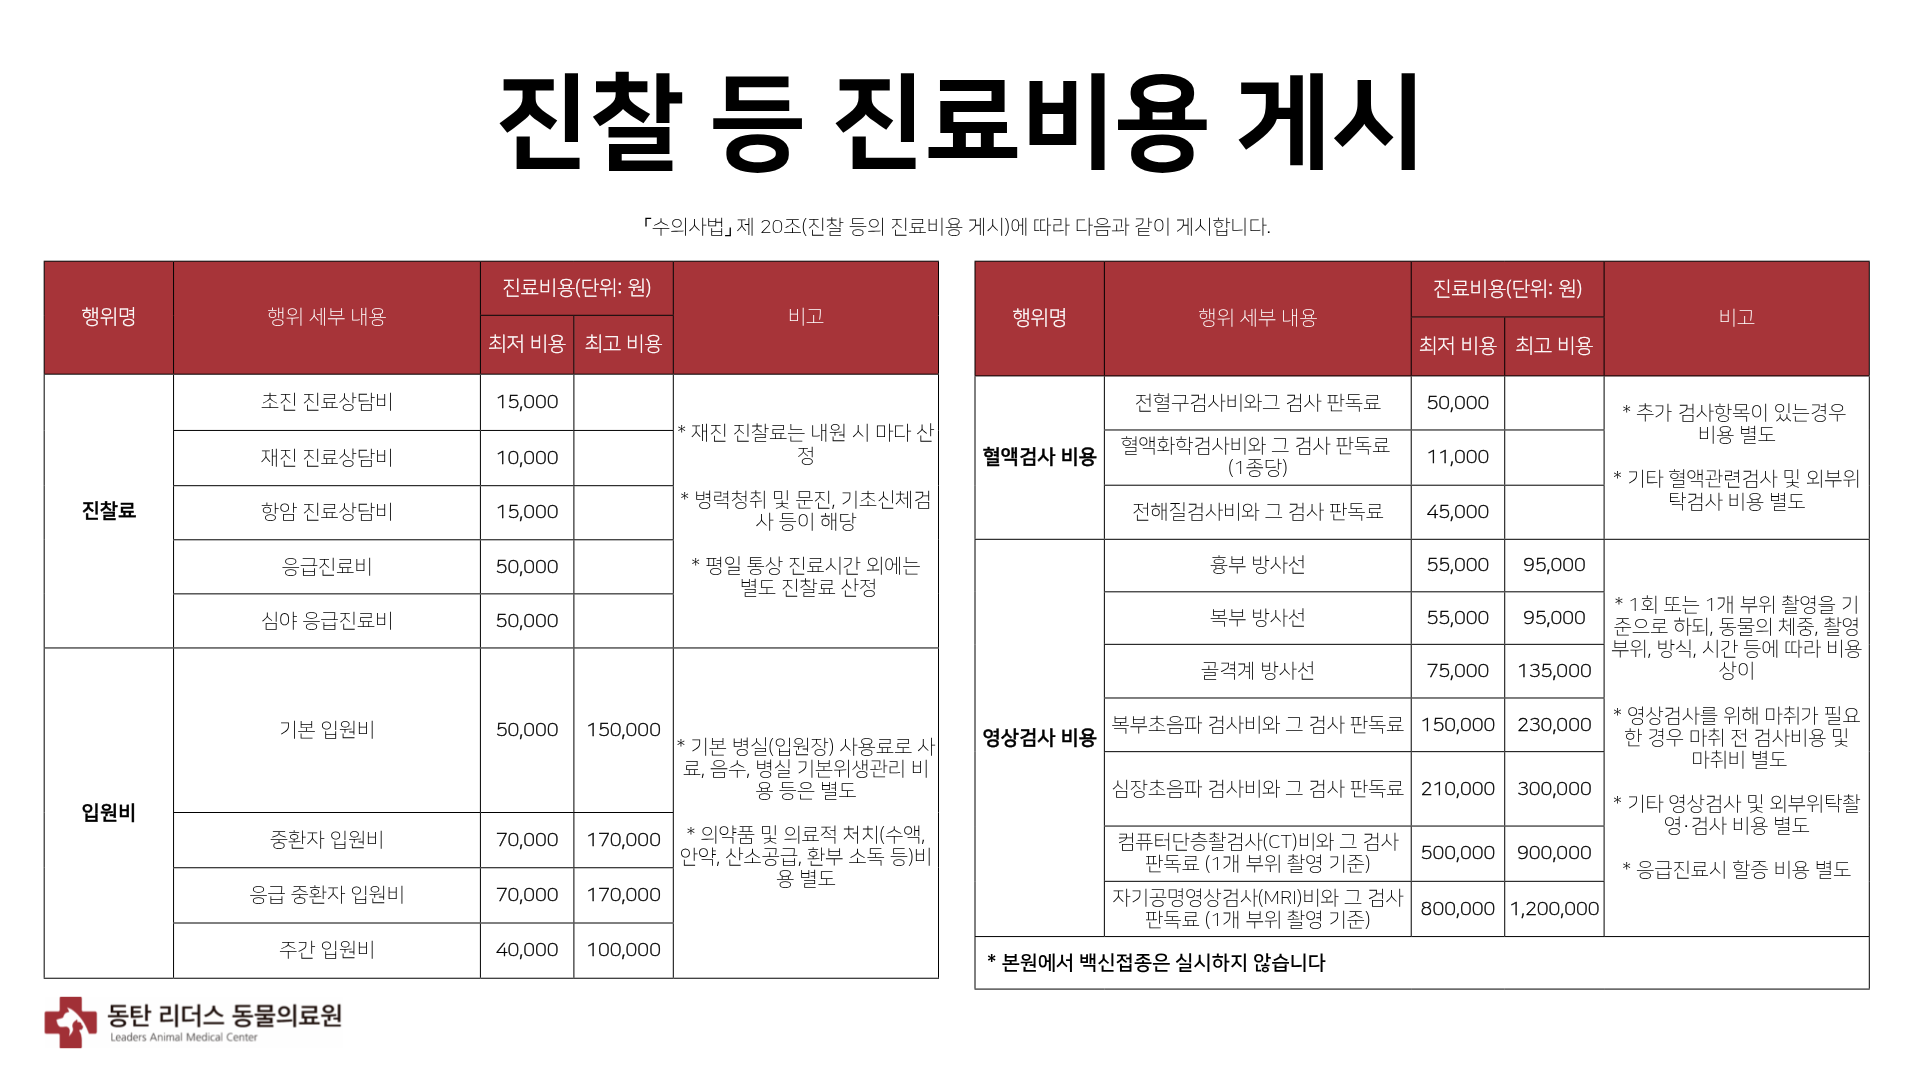

이번에 소개해드릴 환자는 10살의 중성화된 암컷 코리안숏헤어로, 최근 호흡수가 눈에 띄게 증가하고 양쪽 뒷다리를 갑자기 사용하지 못하는 증상이 발생하여 본원에 내원하였습니다. 해당 증상은 단순한 호흡기 문제나 신경 질환뿐 아니라 심장 질환과 혈전 합병증 가능성까지 함께 고려해야 하는 상황이었기 때문에, 정확한 원인 평가를 위해 방사선 검사와 심장 초음파 검사를 진행하였습니다.

방사선 검사에서 다음과 같은 소견이 확인되었습니다.

환자의 방사선검사 사진/ 출처: 24시 동탄리더스동물의료원

- 심장 실루엣이 valentine shape로 관찰되었으며, 실제 측정 결과 심장 크기 VHS 9.7v, VD short axis 5.3v로 심한 심비대가 확인되었습니다.

- 폐의 앞쪽을 따라 주행하는 폐정맥이 미약한 확장된 모습을 보였습니다.

- 양쪽 폐의 후엽에서 폐 실질 하얗게 보이는 소견(alveolar pattern)이 관찰되었습니다.

- 우측 폐 중엽과 후엽 사이 미약한 fissure line( 얇은 선 모양의 변화) 관찰되었습니다.

- 또한 식도와 위 안에 가스가 다량 차 있는 모습이 확인되었습니다.

위 소견을 종합하였을 때, 심한 심비대와 폐수종 소견이 확인되어 고양이 비대성 심근병증(HCM), 제한성 심근병증(RCM) 등을 포함한 심근병증(cardiomyopathy)가 강하게 의심되었습니다.

치료 후 방사선 사진 / 출처: 24시 동탄리더스동물의료원

치료 이후 환자는 심장 크기가 감소하였고 폐수종이 완화되었습니다. 양측 후지 마비도 점차 개선되는 경과를 보였습니다.